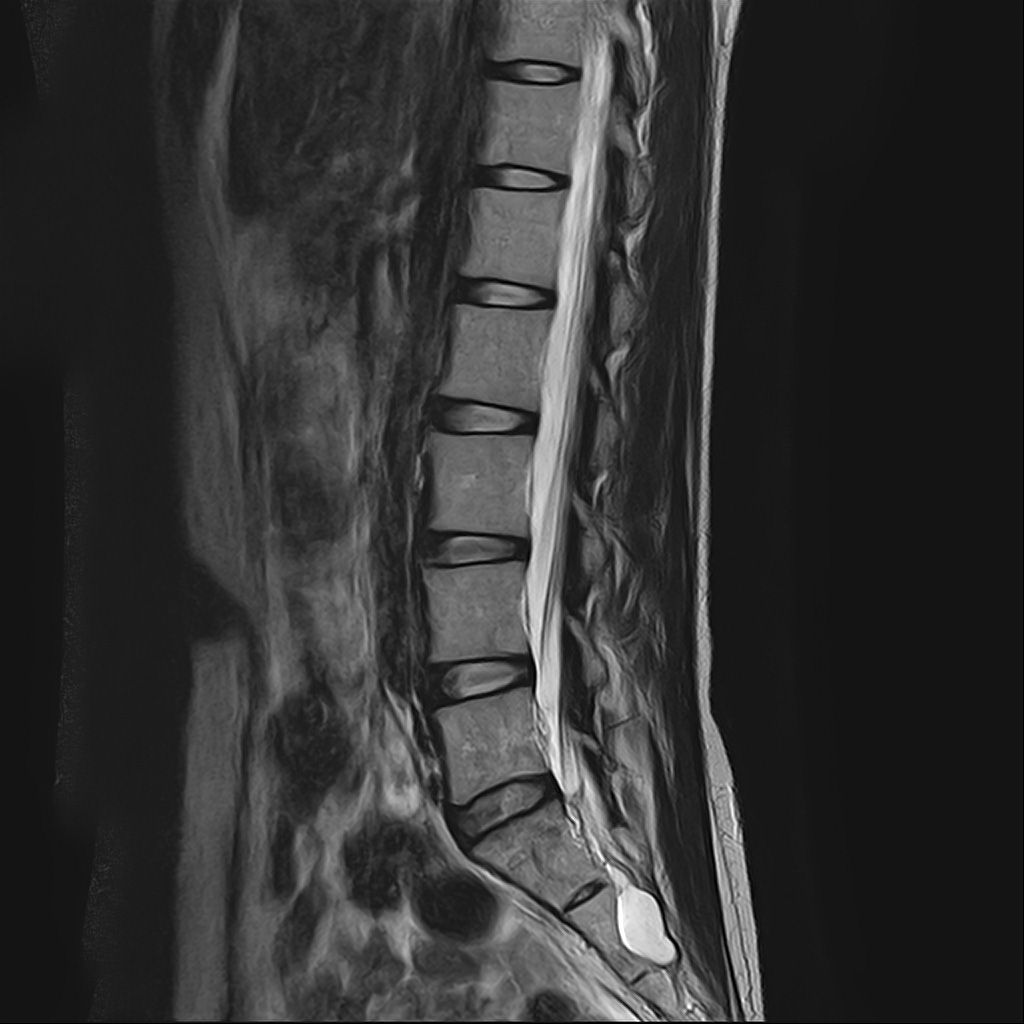

낭종s1-3번까지 꼬리뼈쪽으로 크게 나있다고했고, 단면상으로는 s2,3번이 촬영이 안되서 확인이안된다합니다. 허리디스크가 미약하게 4,5번에 있다고 했는데,

혹시 디스크로 인한 신경눌림인지, 낭종으로 인한건지 알수잇나요?